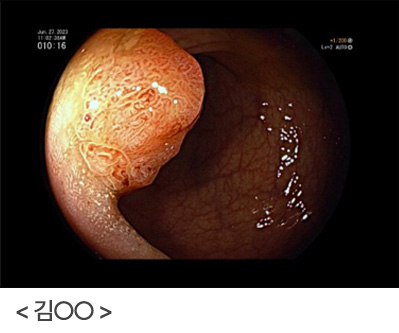

단 한 번의 내시경 검사로, 위암을 진단 못할 수도 있습니다. 위통이나 속 쓰림, 소화불량 등의 증상이 있고 위암일 가능성이 조금이라도 있다면 다시 위내시경을 시행하여 확인하는 것이 중요합니다. 위내시경 시행 후 괜찮다고 안심하지 마시고, 증상이 지속되거나, 위암의 고위험군이라면 지속적인 위내시경 검사를 하시는 것이 좋습니다.